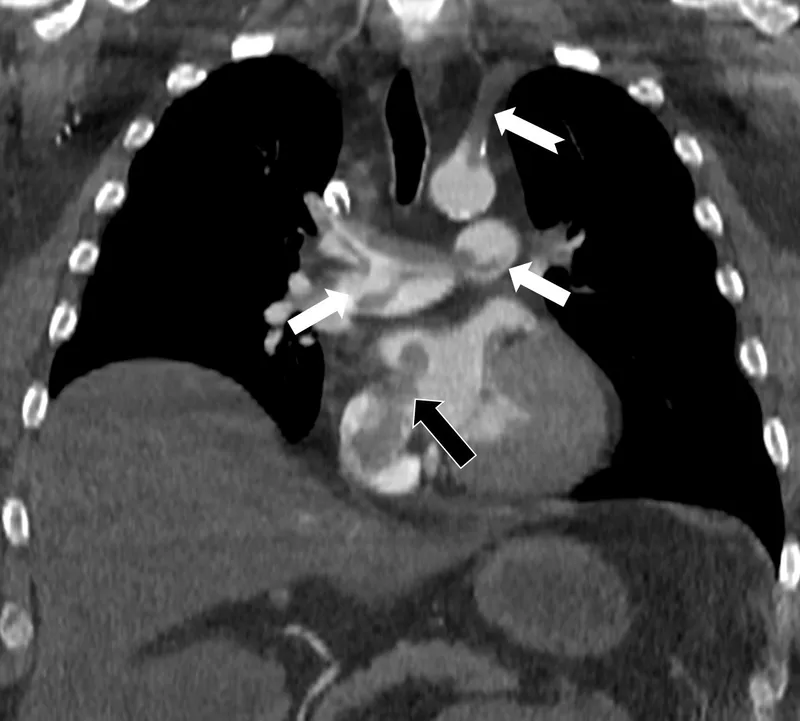

Bir dönem Özel Denizli Tekden Hastanesi'nde de görev yapan Prof. Dr. Nevzat Karabulut'un yaptığı çalışmada; akciğerin bilgisayarlı tomografi anjiyografisi sayesinde toplar damarlardan kaynaklanan pıhtının akciğer damarlarını tıkaması yanında, kalpteki delik nedeniyle kalbin sağ tarafından sol tarafına geçerek ana atardamara ulaştığı ve sol kol damarını tıkadığı gösterildi.

Emboli görüntülemesi konusunda çok sayıda bilimsel çalışması bulunan Prof. Dr. Karabulut, genelde bacak damarlarından kaynaklanan pıhtıların ölümcül olabilen akciğer embolisine yol açması yanında, kalp deliği olan hastalarda ana atardamar yoluyla beyin, kol ve bacak gibi vücudun diğer bölgelerine de geçerek ani damar tıkanmasına (paradoks emboli) bağlı bulgulara yol açtığını belirtti. Prof. Dr. Karabulut'un çalışmasında nedeni bilinmeyen pıhtı atmalarında kalpteki gizli deliklerin mutlaka araştırılması gerektiği vurgulanarak ekokardiyografi ve bilgisayarlı tomografi tetkiklerinin erken ve doğru tanı koymada hayat kurtarıcı rolüne dikkat çekildi.